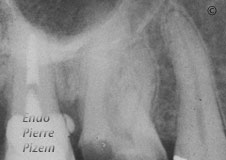

MB1 and MB2 with severe curves first right maxillary molar

You are here: Home / Curved canals / MB1 and MB2 with severe curves first right maxillary molar